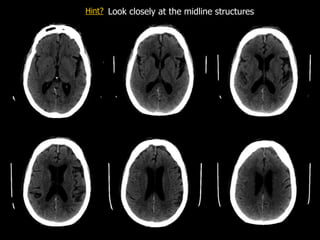

Bonus case  Mr.LR is a 80 y/o male presenting with:  3 month history of delirium  Recent fall from bed  Large scalp laceration  No focal neurological findings  An non-contrast CT scan of his brain is performed

• 70.

Subdural Look closely atthe midline structures Hint?

• 71.

Analysis  Can youspot the abnormalities?  What is your impression?  What would be your top diagnosis?

• 72.

Bonus case -Answer  Mr. LR had a tiny right-sided subdural hematoma  Blood is seen along the left subdural space as well as in the falx cerebri anteriorly (arrows)  The hematoma is acute  Because of its small size, no immediate treatment was required  Follow-up CT scans showed resolution of the subdural hematoma Normal scan for comparison